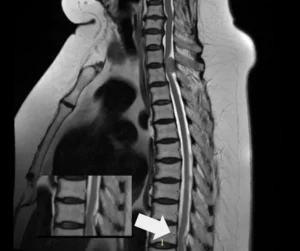

Проведённая МРТ грудного отдела позвоночника выявила две интрадуральные экстрамедуллярные опухоли, вызывающие критическую компрессию спинного мозга. Эти образования были диагностированы за 2–3 года до обращения. Однако, пациентка отказывалась от операции из-за страха, возраста и избыточного веса.

Учитывая возраст пациентки, общую соматическую нагрузку, прогрессирующую неврологическую симптоматику и необходимость срочно устранить компрессию спинного мозга, было принято решение о симультанном (одновременном) удалении обеих опухолей. Это решение позволило сократить время нахождения пациентки под наркозом и минимизировать риски. В таких случаях, когда дорога каждая минута, на помощь приходит спинальная хирургия с использованием современных технологий.

Операция была выполнена двумя командами нейрохирургов онкологов, работающих синхронно через разные хирургические доступы. Мы применили микрохирургическую технику, интраоперационный нейромониторинг и современное анестезиологическое обеспечение. Эти технологии позволили провести вмешательство максимально безопасно, сократить его длительность и уменьшить общую нагрузку на организм пациентки.